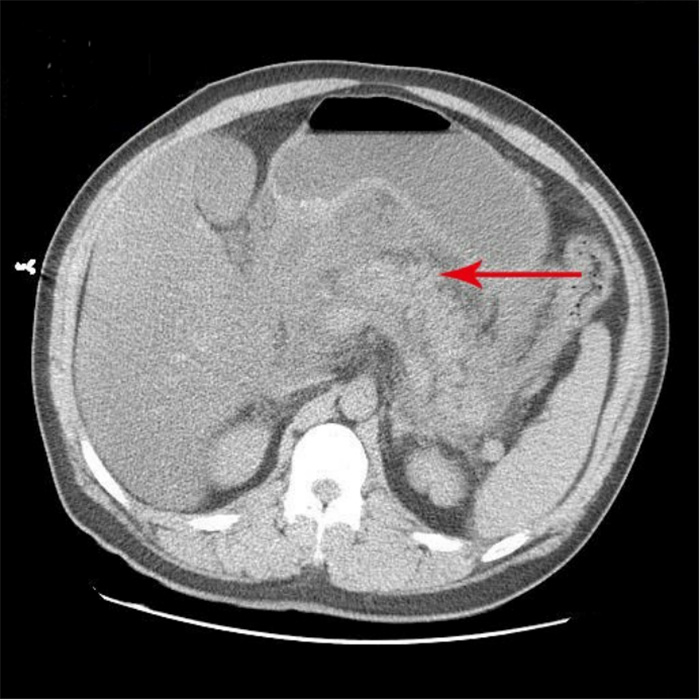

入院第57天,患者再次出现暗红色血便,伴阵发性右上腹痛,无发热、呕血,症状与之前相同。鉴于患者有活动性出血,再次复查胃镜:慢性浅表性胃炎伴糜烂。复查肝功能:γ-GT 844 U/L,TBil 43.6 μmol/L,NCBil 16.6 μmol/L,CBil 27 μmol/L,肝功指标再次回升,γ-GT、CBil明显升高,提示可能出现胆道梗阻。肝胆脾胰腺彩超复查:胆囊肿大、胆囊陈旧性稠厚淤胆(较前无明显变化),胰腺稍大并不均质改变。复查上腹CT:AP复查情况与之前相同,可能有胆囊出血(见图 2)。联合介入放射科行血管造影检查,常规局部麻醉下采用Seldinger技术由右侧股动脉入路,造影发现胆囊动脉分支出血(图 3),超选择胆囊动脉分支用明胶海绵颗粒行栓塞止血(图 4)。同时,行经皮经肝胆囊穿刺置管引流(图 5),病情稳定后带管出院,3月后予以拔除,择期行胆囊切除。

| 胆囊内可见高密度影,A:CT值为62 HU;B:CT值102 HU;C:胰腺假性囊肿引流管 图 2 入院第57天复查腹部CT |

患者病程41 d、57 d查腹部CT分别提示胆囊结石和胆囊内出血的可能性,这是患者入院腹部CT所没有的特征,检测胆囊内病灶CT值为62~102 HU。多学科会诊中大部分专家意见认为胆囊出血临床极罕见,胆囊内病灶并不考虑出血,仍考虑结石可能性大。因患者首次便血后给予对症治疗后便血症状停止,故没有选择血管造影进一步检查明确病因。